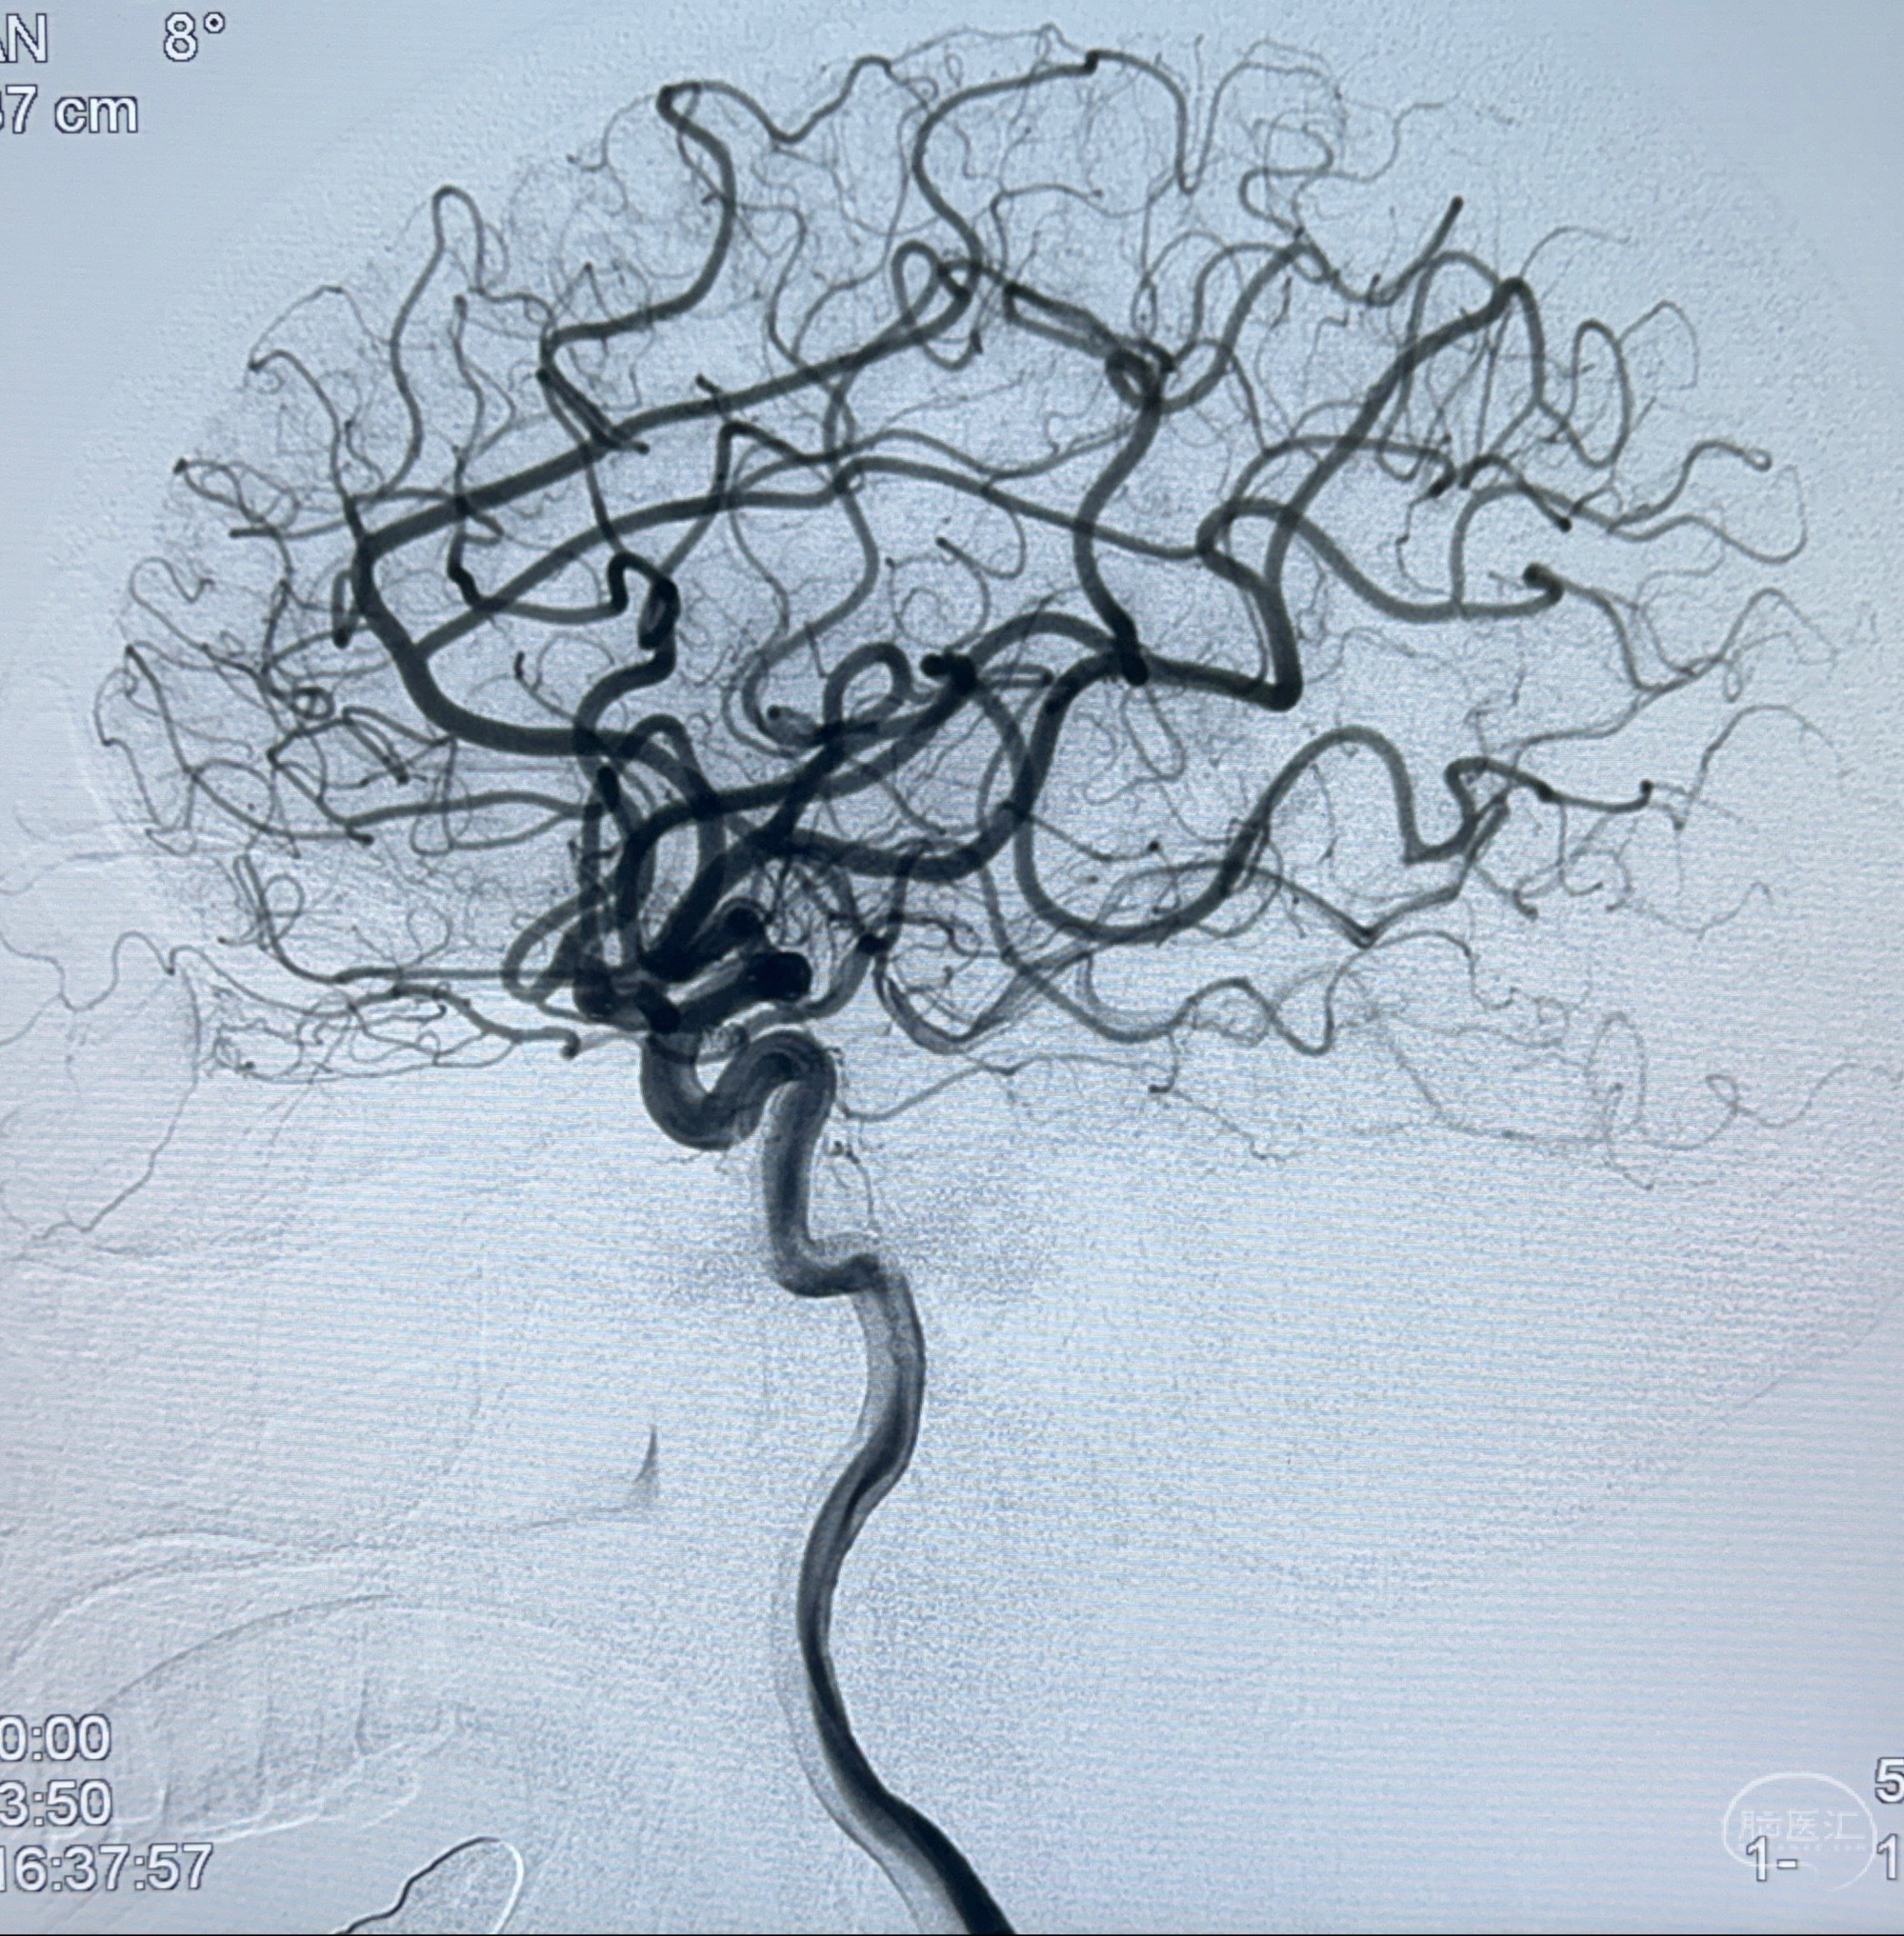

2023-11-24DSA:右侧大脑中动脉下干起始部动脉瘤,约2.3*2.5mm,形态规则

2023-12-04全麻下行支架辅助治疗

S-AB4-20mm

麻醉苏醒佳,遵嘱动作

术后即刻CT